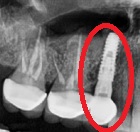

사진에서 볼 수 있듯이 보통 치주질환으로 인한 발치는 염증이 심해서 치아를 잡아주고 있는 잇몸뼈를 없어지게 만듭니다.

잇몸뼈를 없어지게 하는 주 요인인 해당치아를 발치하면서 염증조직을 깨끗하게 긁어내고 소실된 잇몸뼈가 어느 정도 다시 생길 수 있는 시간을 3개월 정도 기다립니다. 따라서 이렇게 잇몸뼈가 많이 없거나 염증이 x-ray상에 나타날 정도로 많은 경우 발치 후 바로 식립 하는 건 감염에 의해 임플란트를 실패할 확률이 많아져요. 때문에 이런 경우에는 발치 후 바로 임플란트를 식립하는건 권유드리지 않습니다.